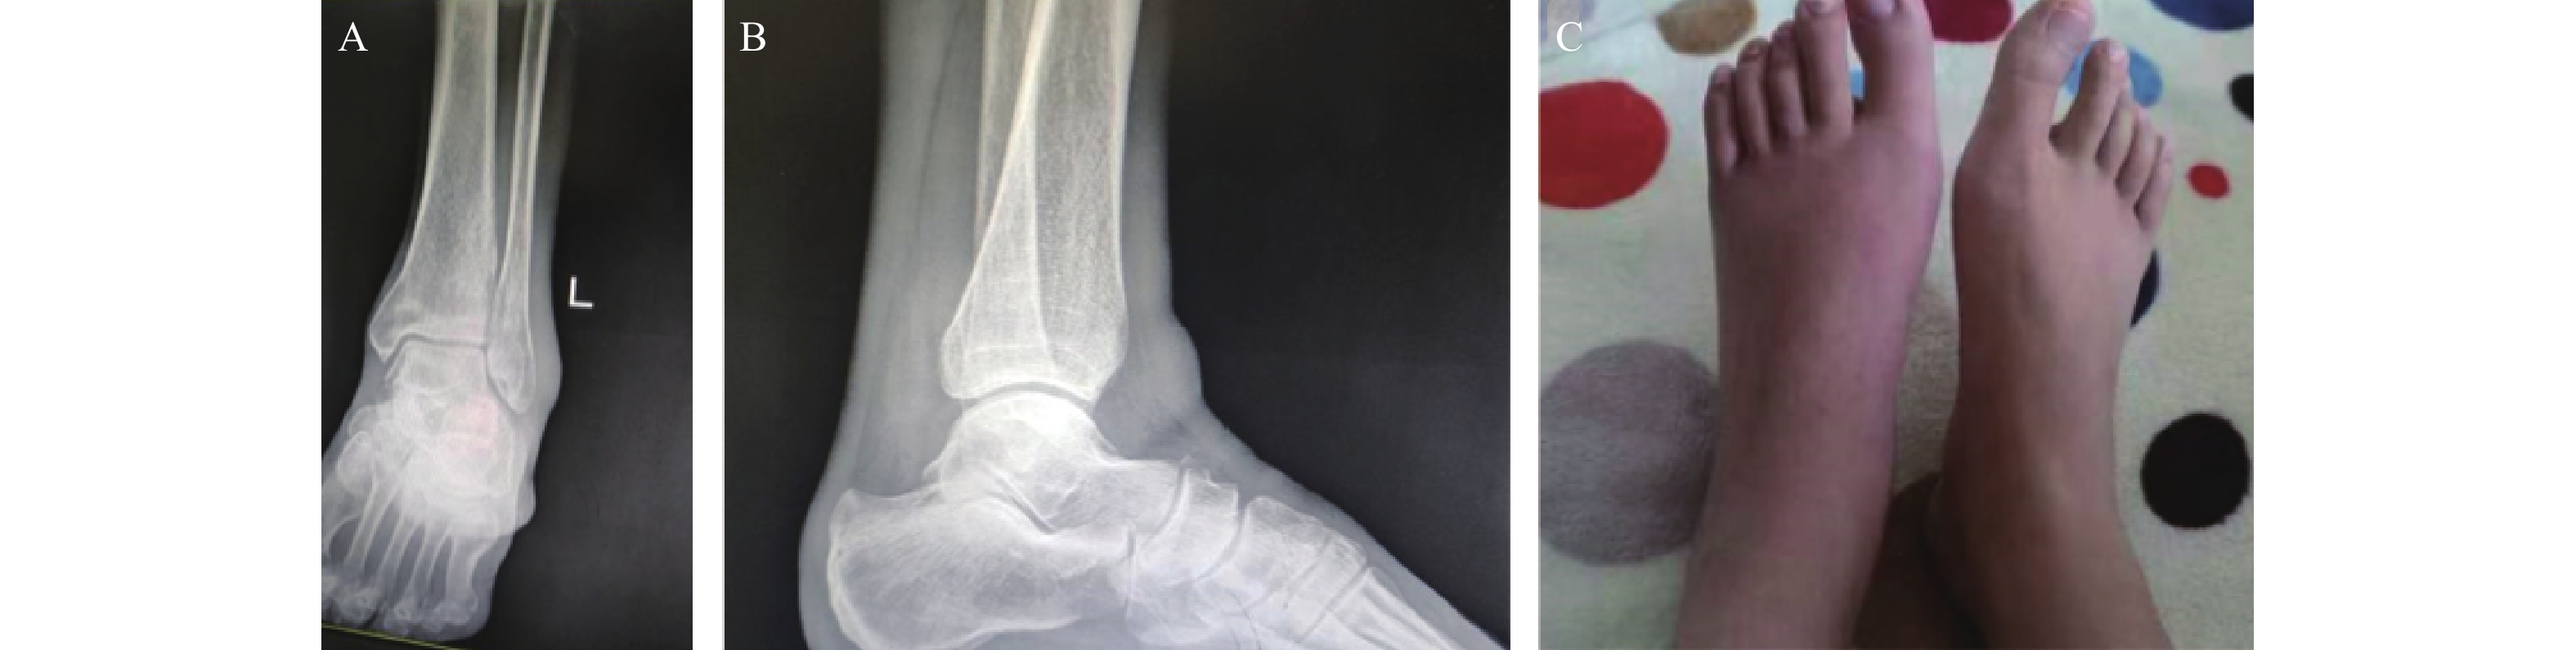

• 图  1  Physio Space平衡板运动控制训练

Figure  1.  Physio Space balance board motion control training